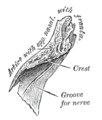

The inner surface is concave from side to side, and is traversed from above downward, by a groove for the passage of a branch of the nasociliary nerve.

Right nasal bone. Outer surface. Right nasal bone. Inner surface.

Right nasal bone. Inner surface. Close up of side view of the skull.